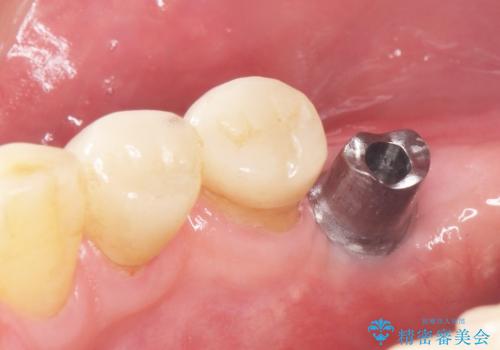

患者様のご希望により、抜歯後インプラント治療を行いました。

- ¥550,000 (インプラント、骨増生、アバットメント、クラウン) ※税込費用は治療当時の料金となります

奥歯でしっかりと咬むことができるようになり、大変喜んで頂けました。

クラウンの種類:オールセラミッククラウン スタンダード